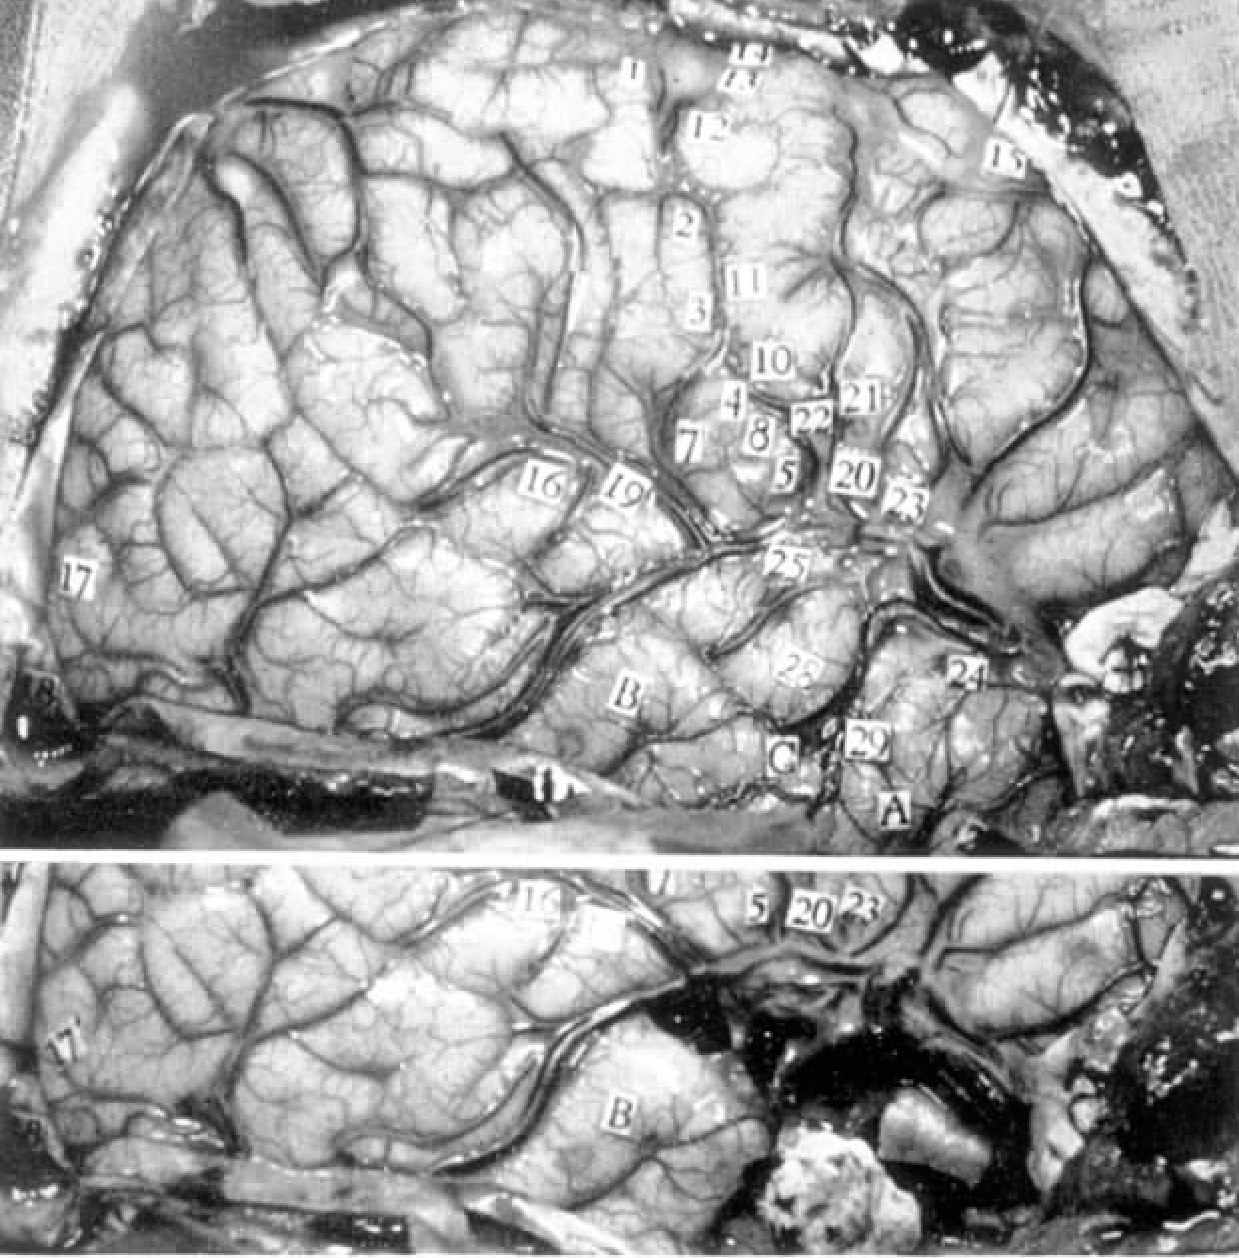

右侧外侧裂部(见图3-14和图3-15)。

图3-14 病例R.Su.图为右侧大脑半球的照片,上图为未切除的照片,下图为切除后照片(刺激结果详见文中描述。在颞叶表面以下可见外伤性损害)

图3-15 病例R.Su.数字标签为有阳性刺激结果的位置(详见文中描述。虚线表示要切除的颞叶区域)